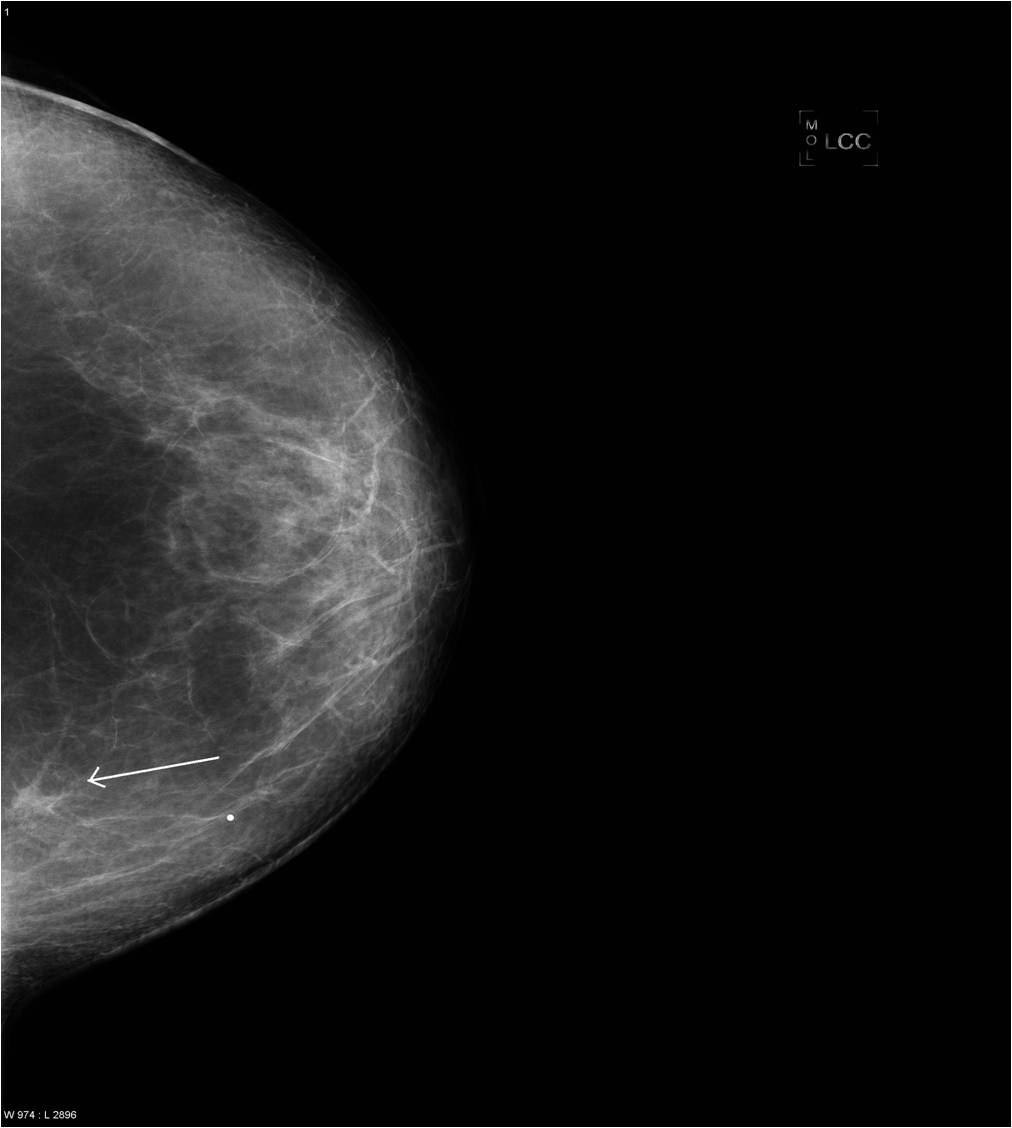

2. Digital mammography has displaced the analogue technic for today almost everywhere: (pictures 1,2,3) phosphorous plate or direct digital methods. For breast imaging the latter is the method of choice. Phases of image production separate. The image is produced on the detectors, but appears on the high resolution monitor and can be stored as a digital data set at various storage mediums (e.g.: CD, hard disk drives).

Image

Picture 1.

Picture 2.

Picture 3.